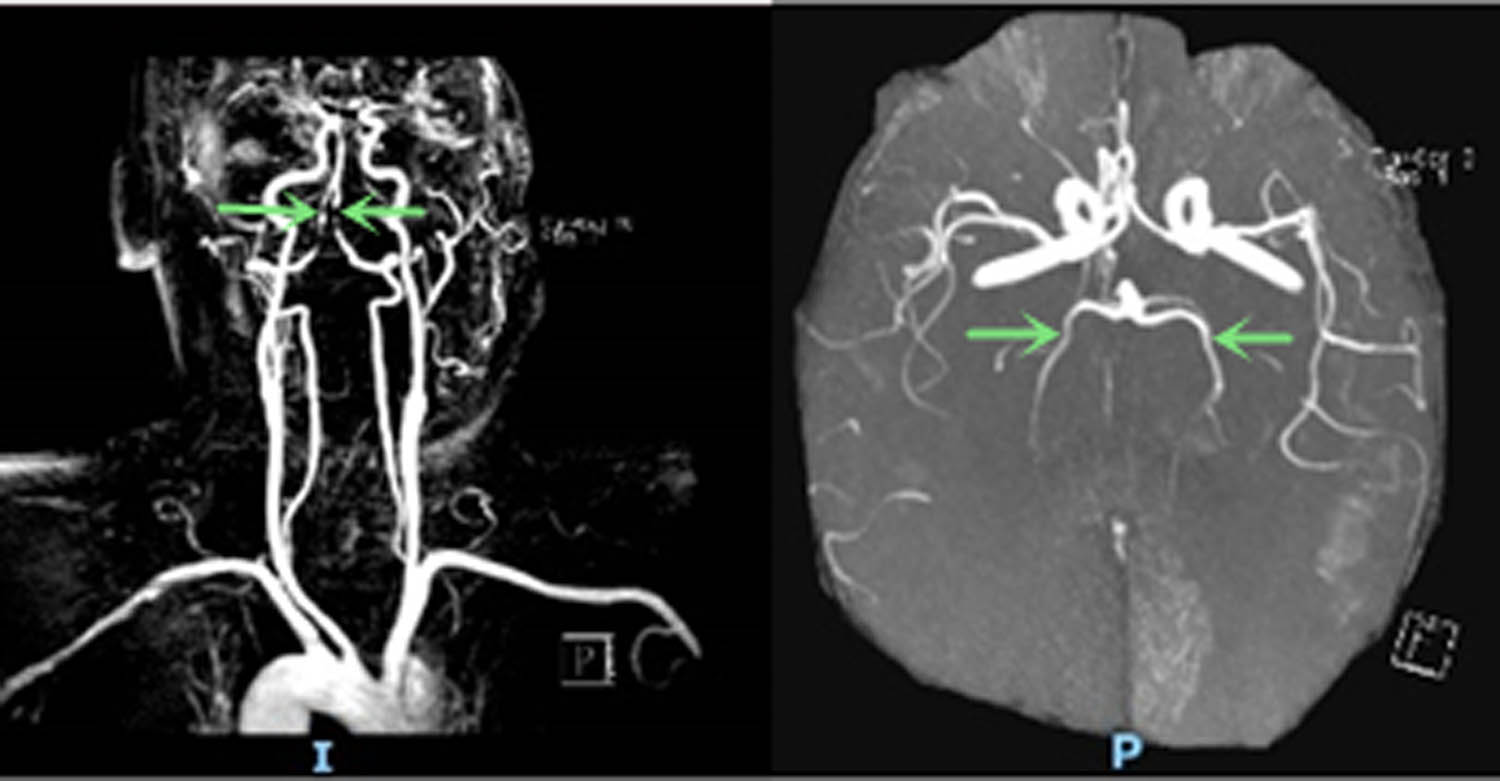

Head and neck CT angiography (CTA) was performed, which showed significant stenosis in the basilar artery, and occlusion in the V4 segment of the left vertebral artery (Figure 2). Digital subtraction angiography (DSA) showed significant stenosis in the V4 segment of the right vertebral artery, occlusion in the V4 segment of the left vertebral, and left posterior cerebral arteries (Figure 3). Thrombectomy was initially considered, but it was aborted due to hemodynamic instability. CT brain the next day showed acute infarcts in the left parieto-occipital region and the left thalamus (Figure 4). Repeat magnetic resonance angiography (MRA) head and neck was performed 25 days after presentation, which showed persistent stenosis in the V4 segments of the bilateral vertebral arteries, but patent bilateral posterior cerebral arteries (Figure 5).

Repeat head and neck MRA (25 days after symptom onset) showed persistent stenosis in the bilateral V4 segments of the vertebral arteries and patency in bilateral posterior cerebral arteries (arrow).